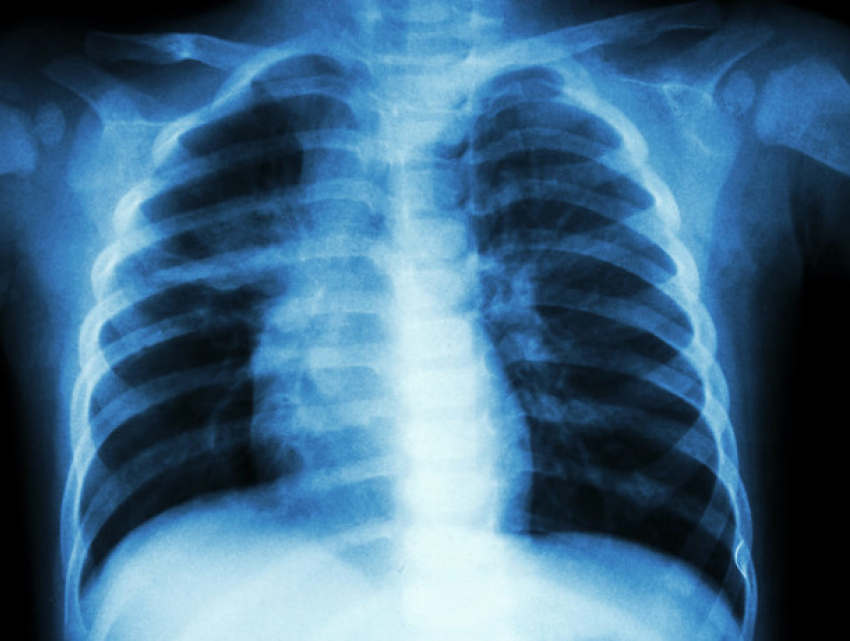

В Кишиневе бушует пневмония: сильнее остальных страдают дети

В столице на 25 процентов увеличилась заболеваемость пневмонией. Об этом сообщил сегодня заместитель начальника Главного управления медико-социальной помощи Владимир Болокан на оперативном совещании муниципальных служб, передает Молдпрес.

По его словам, из общего числа случаев более 63 процента зафиксировано у детей.